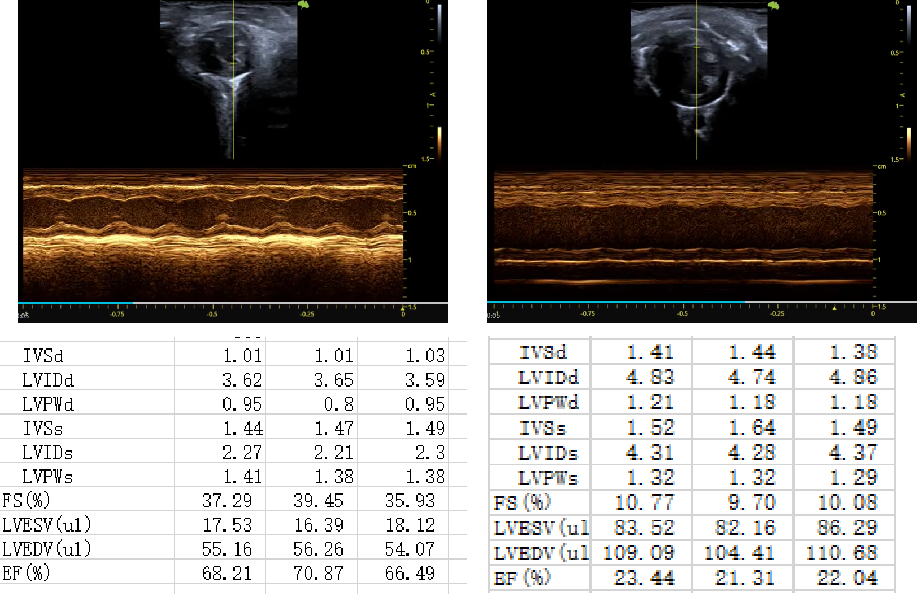

二、小鼠慢性心衰模型

造模:C57bl/6J小鼠麻醉后,在胸骨上缘下方处,横向剪开一个开口。在胸骨上缘下方处,横向剪开一个开口。使用缝合线穿过主动脉弓部,连同垫针将主动脉弓部结扎,然后拔出垫针。逐层缝合伤口。放入保温箱待小鼠苏醒后放入鼠笼。8周后进行模型验证。

1.造模过程

2.模型验证

左室射血分数EF值低于50%是心衰, 40%-50%:轻度心衰,在30%-40%:中度心衰,如果低于30%属于重度心衰。心脏左室短轴缩短率FS值低于25%,表明左心室缩短率明显降低。